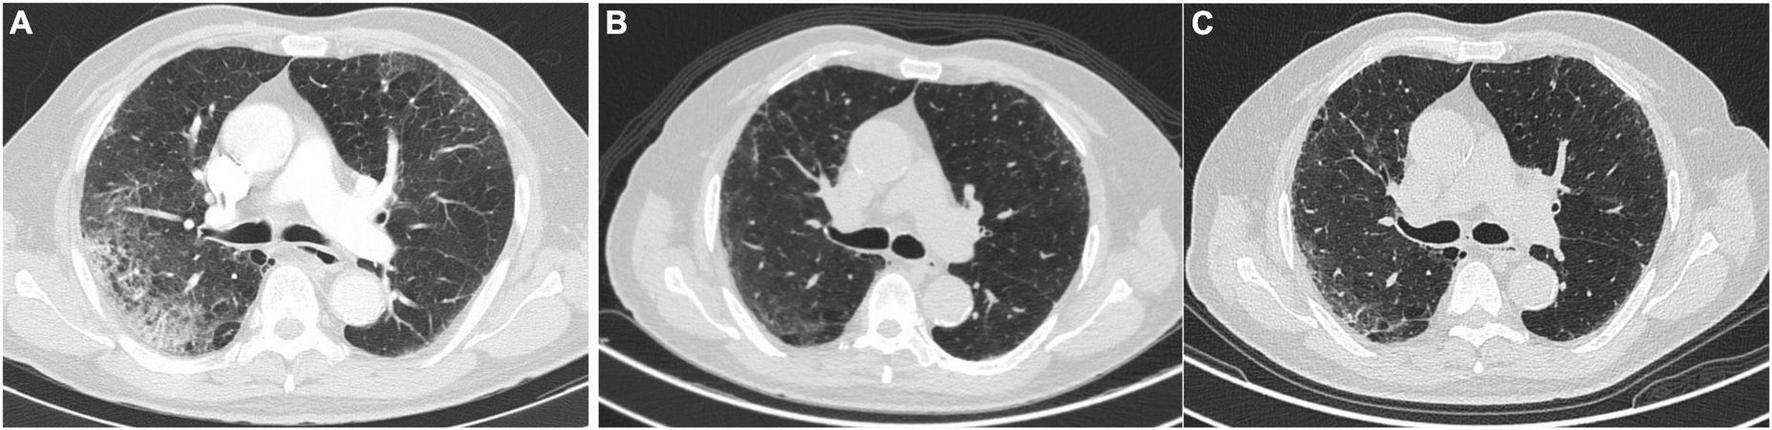

On admission, 92.4% of the patients had CT scans typical findings of SARS-CoV-2 infection, with no differences between the NLCT and ALCT groups (p = 0.412). In the follow-up 6 months after hospital discharge, the most frequent pattern of alteration in the ALCT group was the GGO (31.7%), followed by the reticular pattern in 2.5%, and no patient presented findings of traction bronchiectasis or honeycomb (Figure 2).

FIGURE 2

Changes in the CT scan in a patient with COVID pneumonia. (A) Upon admission. (B) At 3 months of follow-up. (C) At six-month follow-up.